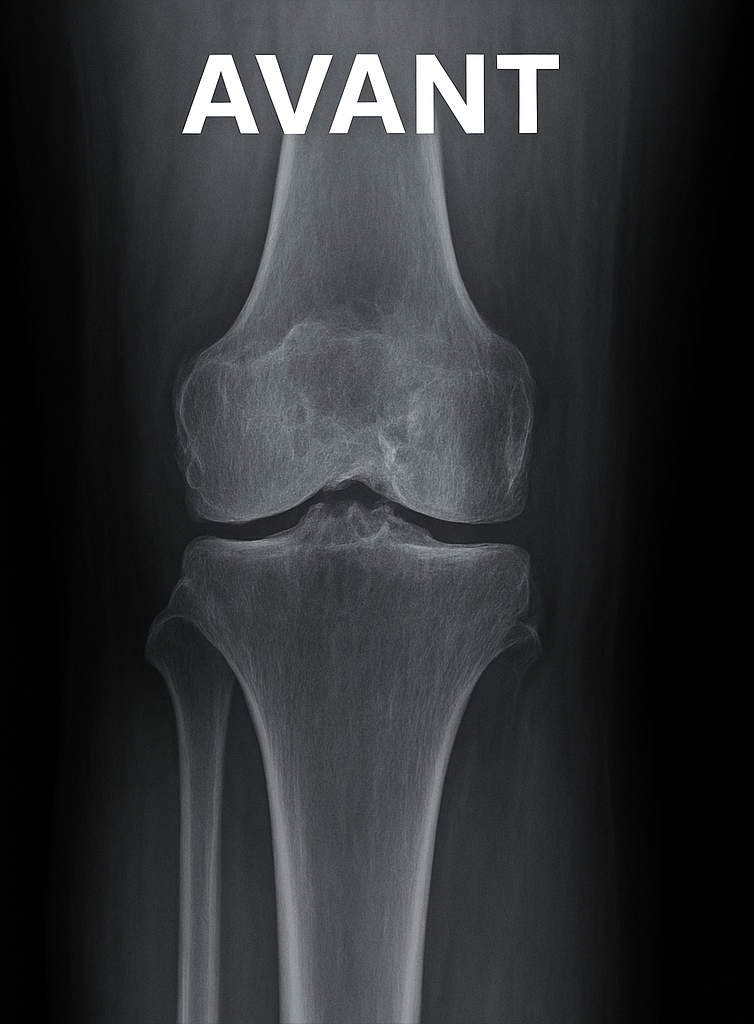

Illustration radiologique

Prothèse du genou